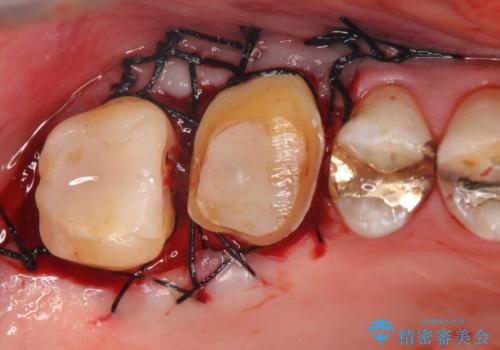

右上6,7の金歯を外したところ、虫歯が歯茎より深い位置まで進行していたため歯周外科を行いました。

虫歯が進み歯茎より深くなってしまうと、虫歯を取り残してしまうリスク、樹脂の硬化の妨げ、補綴物の不適合、歯肉炎・歯周病のリスクの増大等様々な弊害が起こり得ます。

そのため当院では歯周外科手術(歯茎を下げる手術)や歯の挺出による、虫歯が歯茎より深いという問題の解決を推奨しております。

- 外科手術のため、術後に痛みや腫れ、違和感を伴います